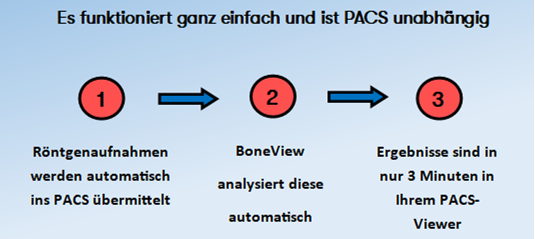

Wie es funktioniert